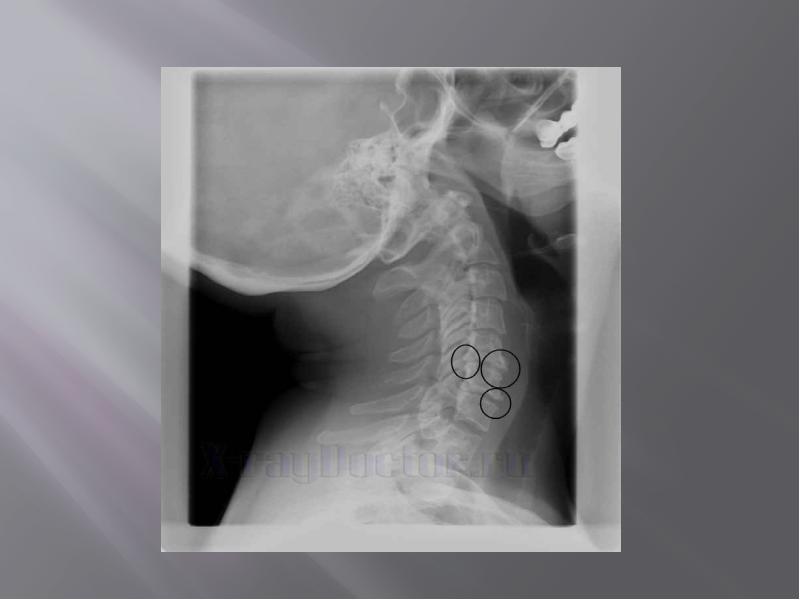

- 43. Рентгенография позвоночника при остеохондрозе позволяет выявить изменения позвоночника, такие как: Рентгенография

- 44. Обзорная рентгенография в 2-х стандартных проекциях (боковая и задняя) позволяет оценить